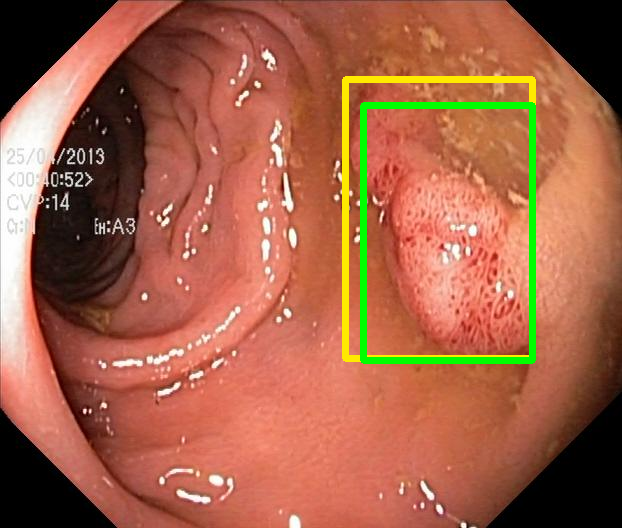

We evaluate the resulting object detection models using the test data, which is pre-processed in the same manner as the validation data, with AP@[.5:.95] (AP for conciseness), AP@.5 (AP50), and AP@.75 (AP75) computed for predicted bounded boxes with a confidence score \geq0.05. For all metrics, a higher value indicates better performance. The results are presented in Table VI, and some examples for predicted bounding boxes with a confidence score \geq0.5 are shown in Fig. 1.

Figure 1: Targets (yellow bounding boxes) and predictions (green bounding boxes) for two randomly selected instances of the Kvasir-SEG test set. For conciseness, we denote ResNet50s with RN, ViT-Bs with VT, Hyperkvasir-unlabelled with HK, ImageNet-1k with IN, MoCo v3 with MC, Barlow Twins with BT, MAE with MA, supervised pretraining with SL, and no pretraining with NA-NA.